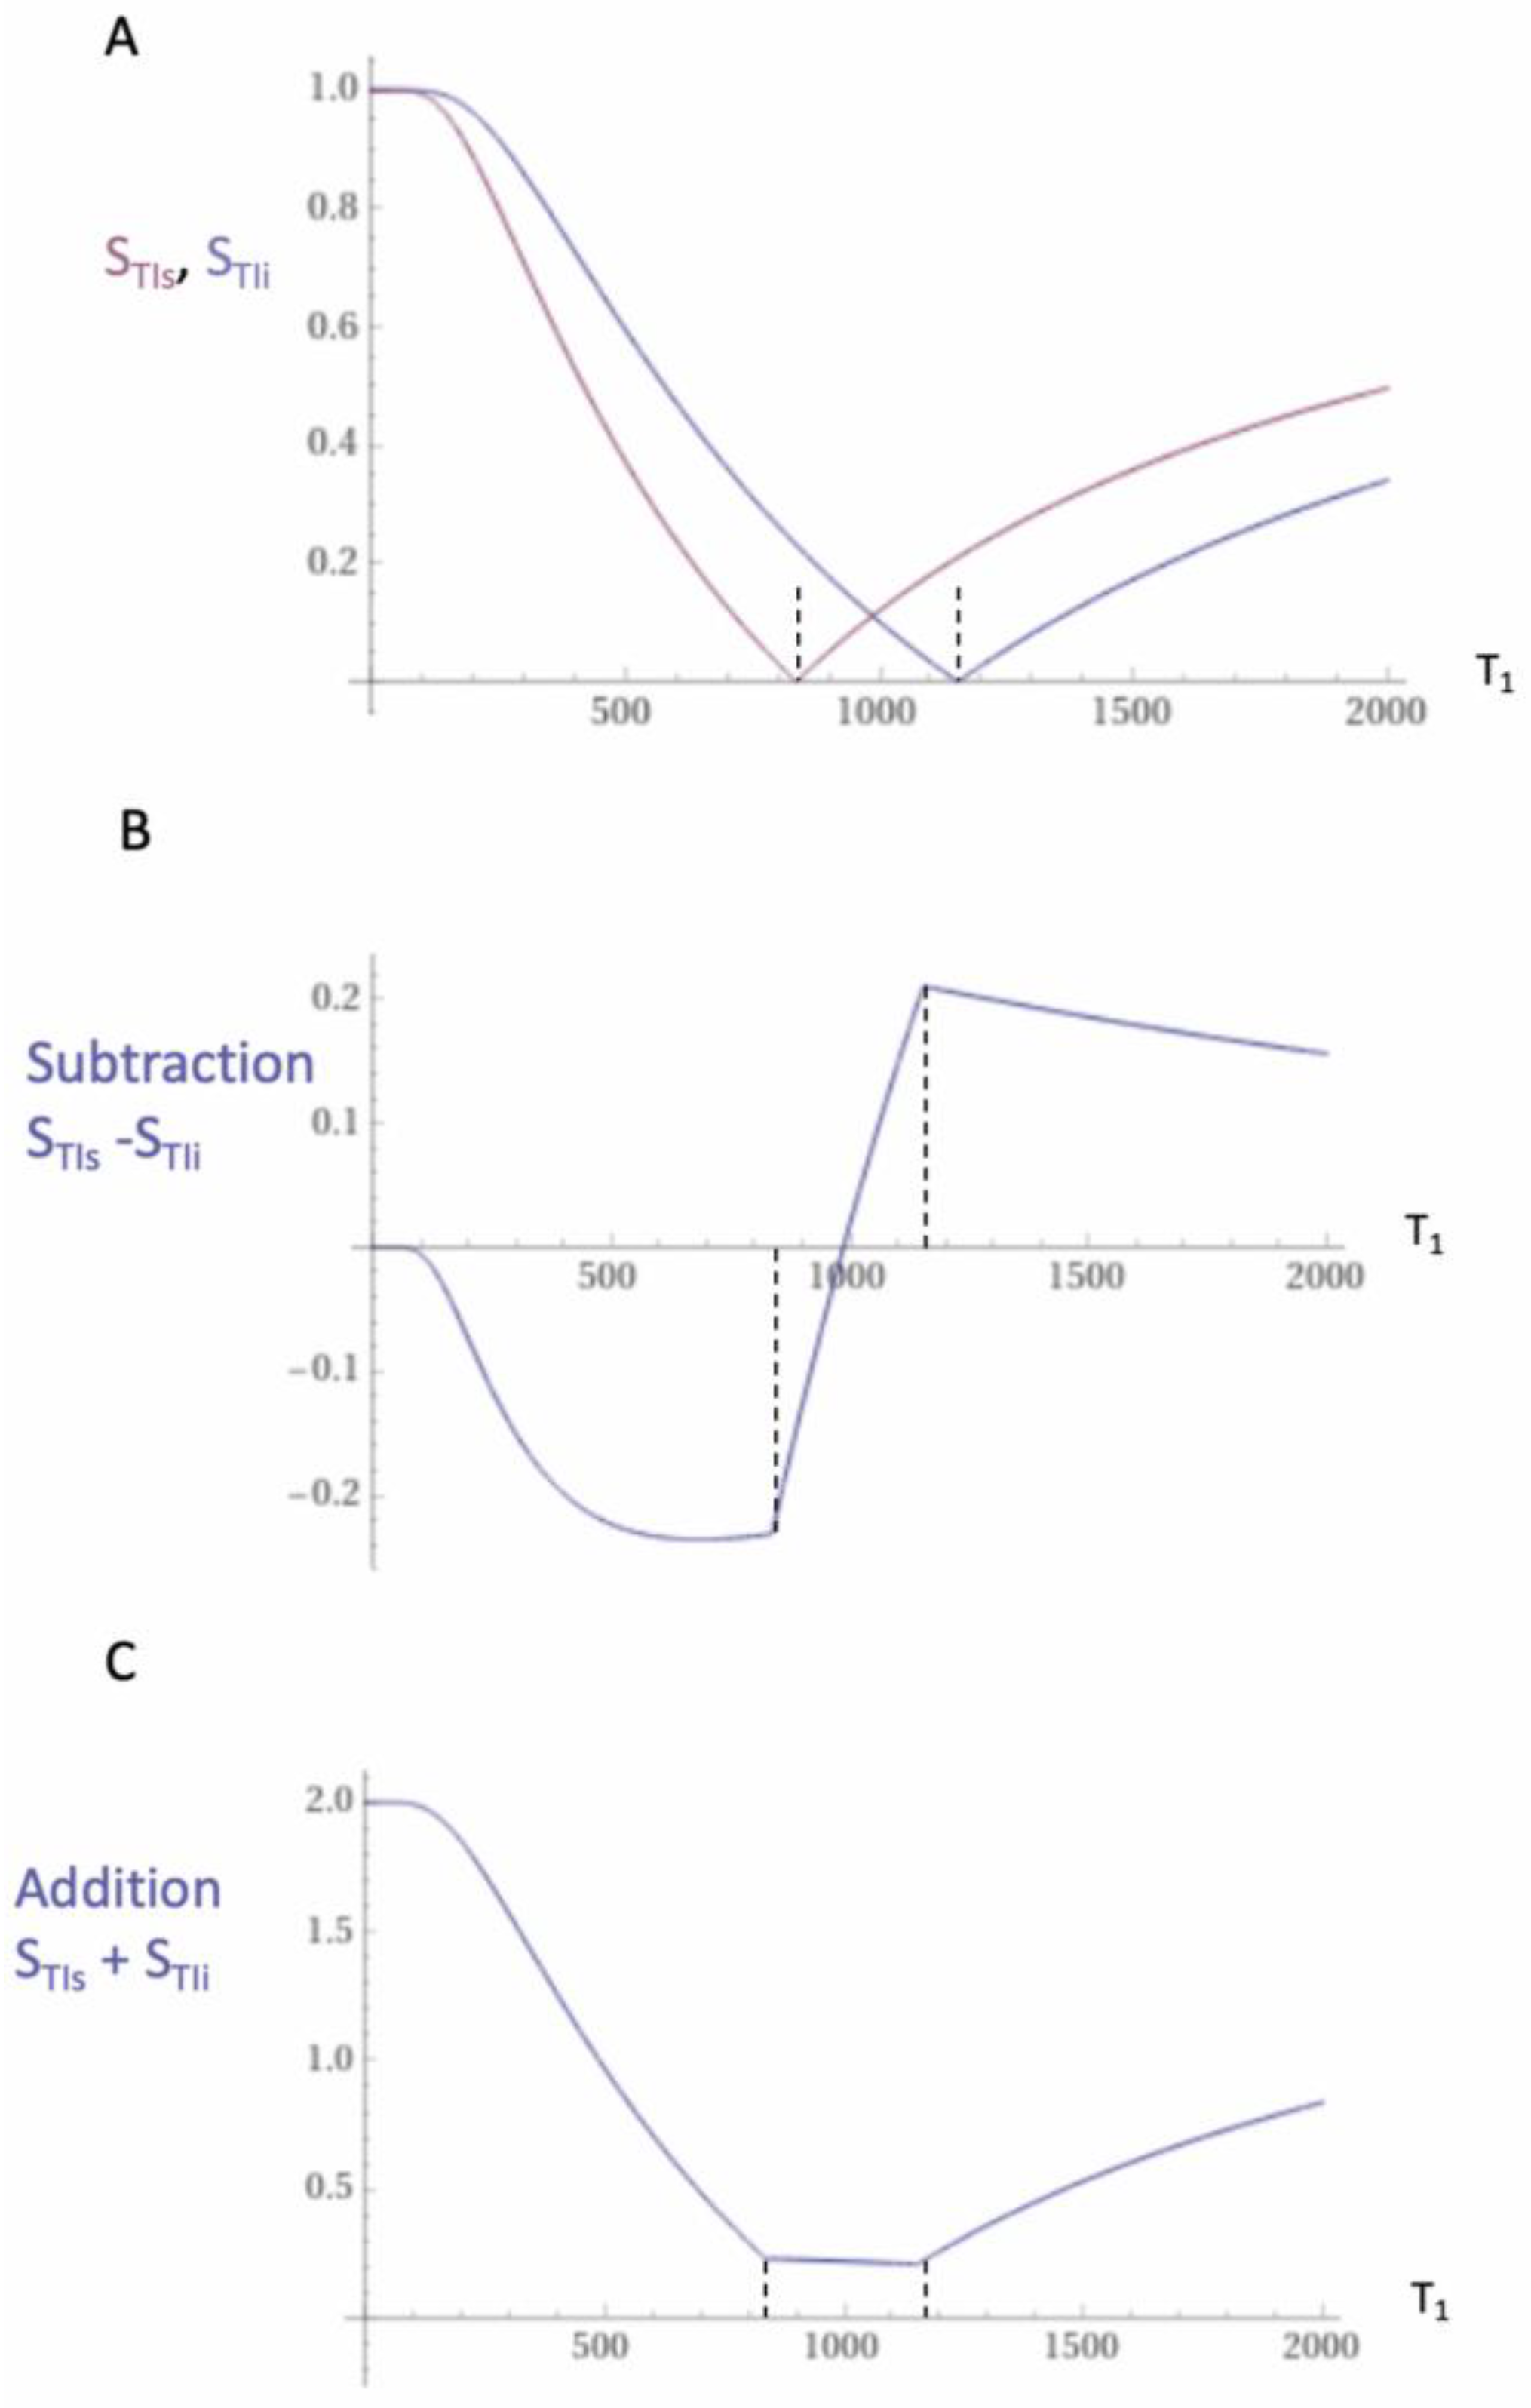

2. Basic Physics

2.1. Tissue Property Filters (TP-Filters) and the Inversion Recovery (IR) Sequence

| 1 | IR, TIs | STIs = 1 − 2e−TIs/T1 | Figure 1, Figure 2 and Figure 3 |

| 2 | IR, TIi | STIi = 1 − 2e−TIi/T1 | Figure 1, Figure 2 and Figure 3 |

| 3 | SIR | SSIR = STIs − STIi | Figure 1 |

| 4 | dSIR | Figure 2 and Figure 3 | |

| 7 | dSIR, SdSIR | (in mD) | Figure 2 |

| 8 | dSIR, T1 | (in mD) | Figure 2 |